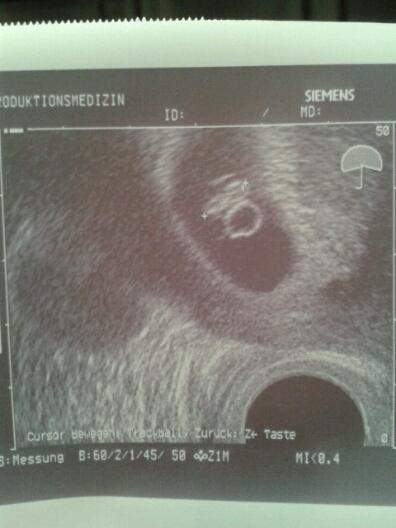

Hallo ihr lieben... umso öfter ich mein us bild von meinen wurm anseh umso komischer ist es ich finde da ist viel zu viel drinnen wenn ich mir andere bilder so anseh ich sehe einen kreis (dottersack) ober den wurm und einen rechts daneben oder was sagt ihr dazu... schaut euch mein bild an und sagt mir eure meinung bitte... hab erst wieder am 29. termin :)

ich finde dein bild sieht anders aus... anders als bei mir sieht man eindeutig das baby und den dottersack... beimir eigentlich auch aber ober dem baby ist noch was :o